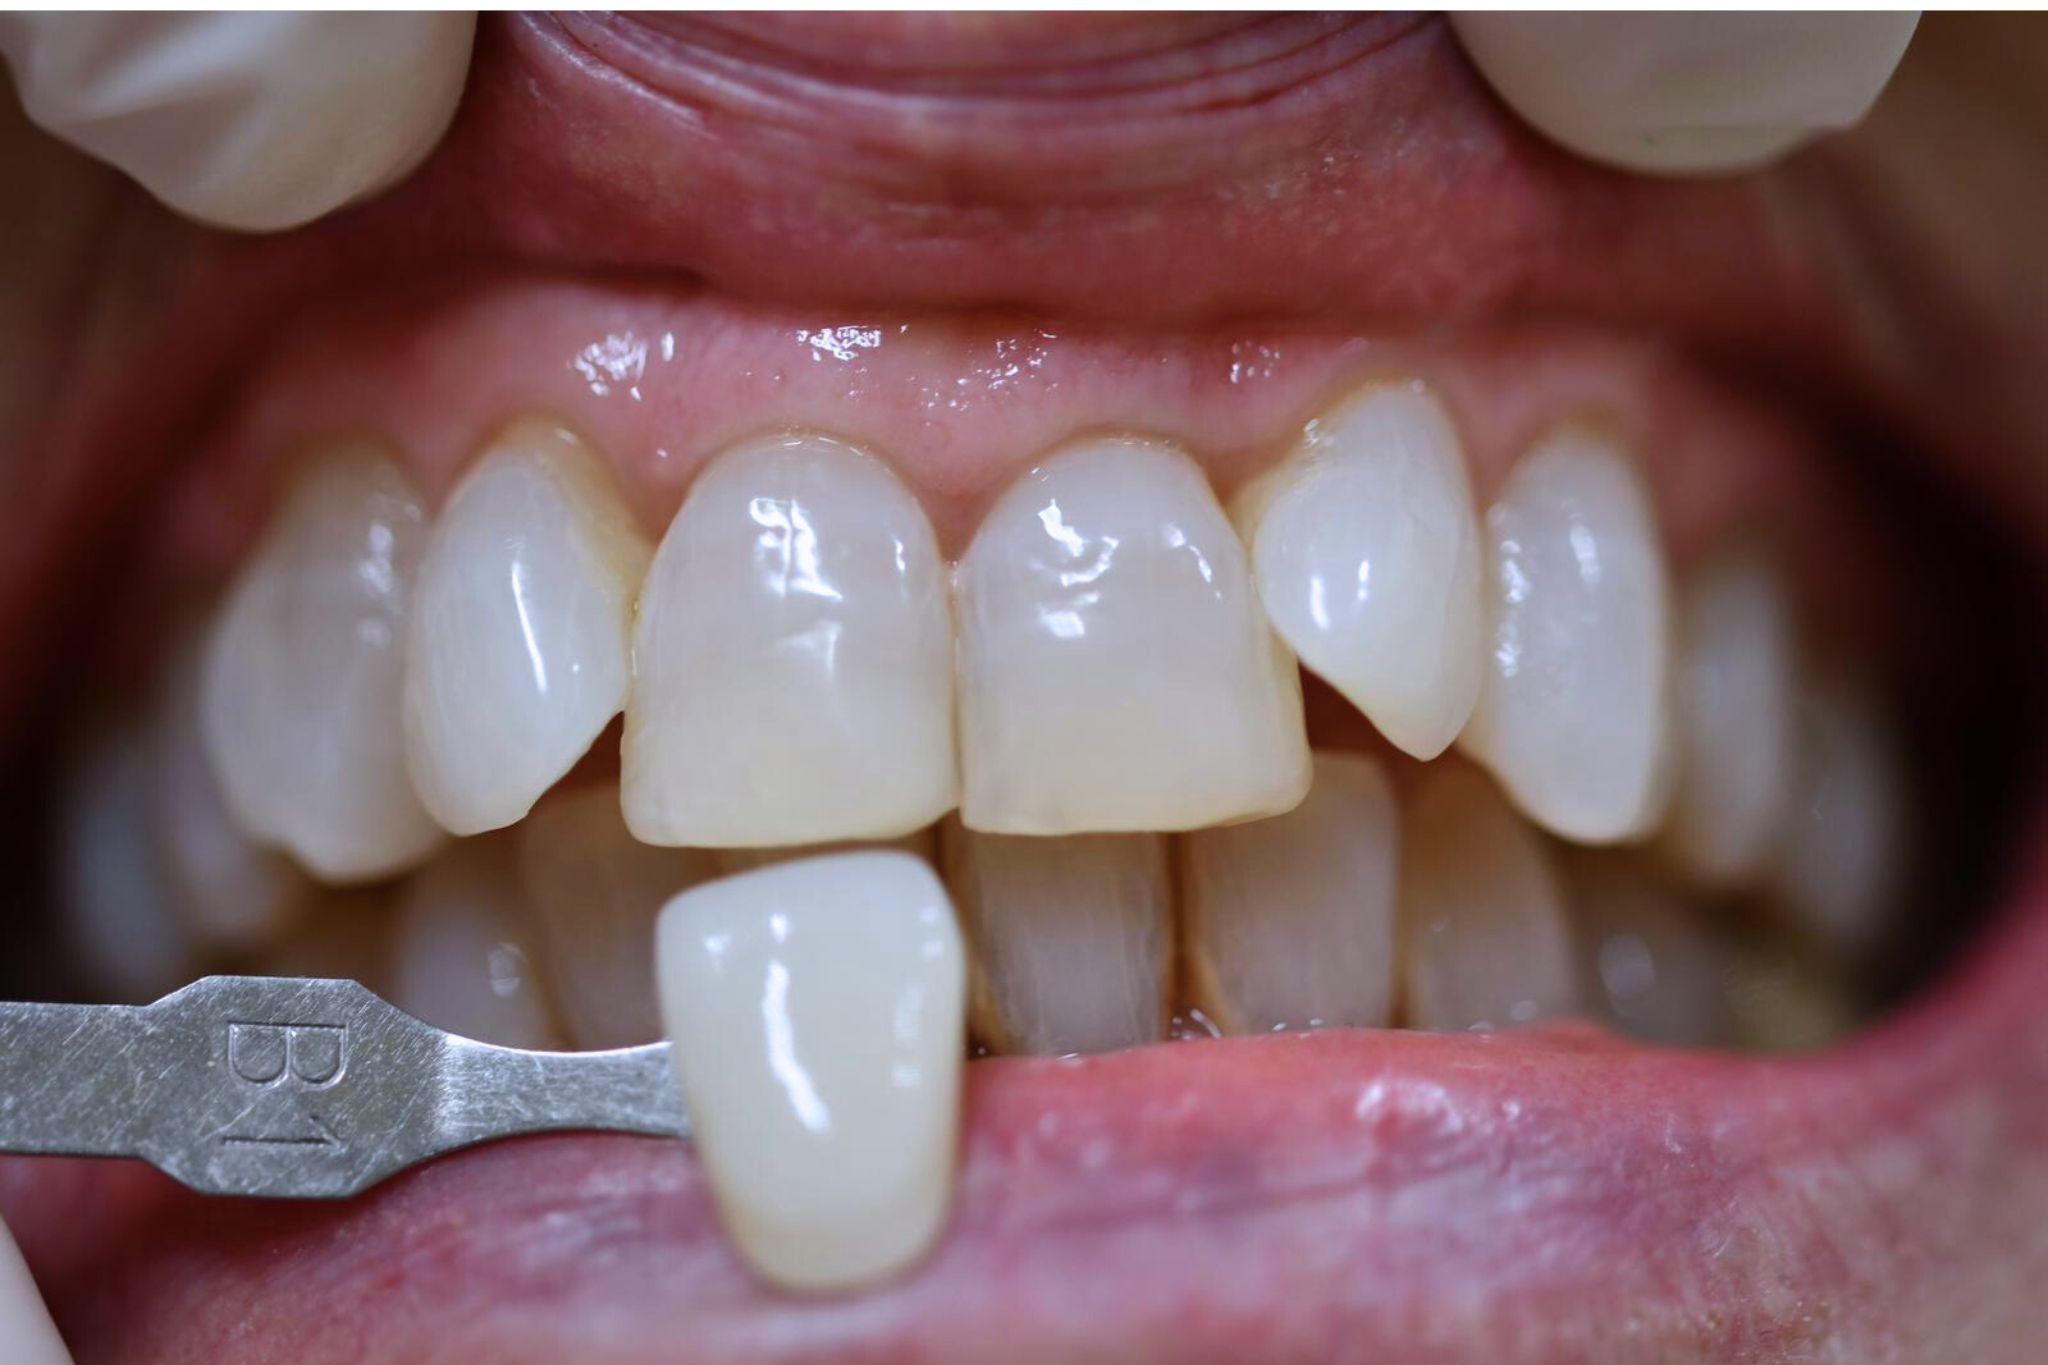

Il trattamento sbiancante medicale è un trattamento ad alta concentrazione di perossido di idrogeno in grado di produrre ottimi risultati in un’unica seduta, anche partendo da tonalità molto scure. ideale per affrontare le situazioni più difficili, come denti con colorazioni estremamente scure o affetti da discromie derivanti da terapie farmacologiche, oppure per tutte quelle situazioni in cui è richiesto un colore molto bianco per necessità di immagine (ad esempio i matrimoni) o di lavoro.